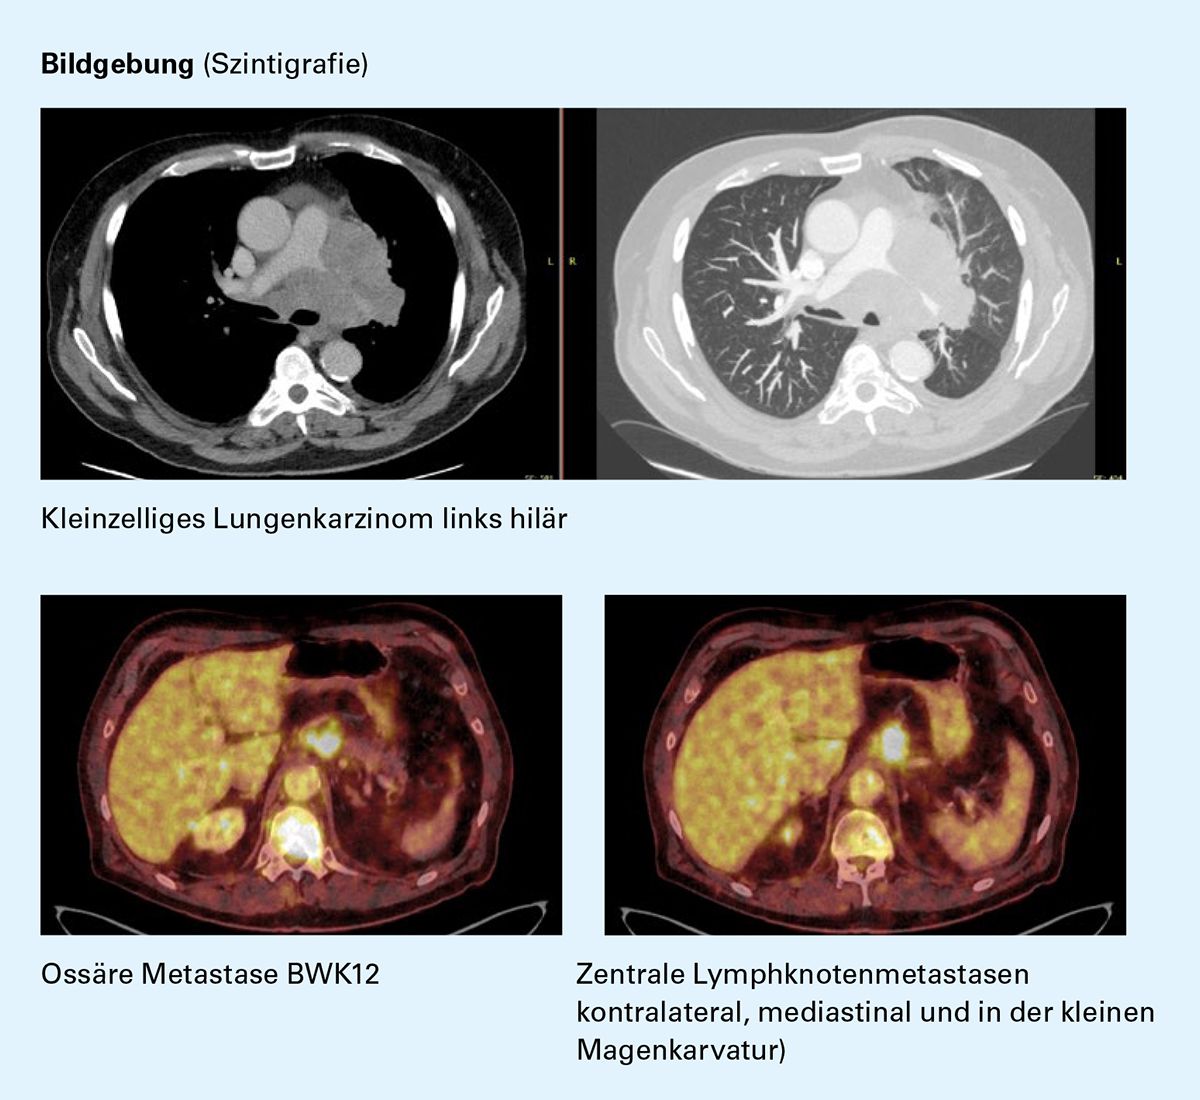

Diagnoseweg (10/2020)

- Röntgen-Thorax: RF links zentral

- CT-Thorax: Pneumonie OL links und RF links zentral

- PET-CT: Ossäre Metastasierungen (BWK5/12, LWK1, in Höhe des Pfannendaches des rechten Hüftgelenkes)

- MRT-Schädel: Keine Metastasierung

- Bronchoskopie und Histologie: SCLC

- Labor: NSE 61 μg/l (NB <19,5), CEA 23,6 ug/l (NB <5,0), CYFRA 21-1, 34,8 ng/ml (NB <3,0)

Erstdiagnose (11/2020)

• mT4mN3mM1c (OSS), UICC8 IVB